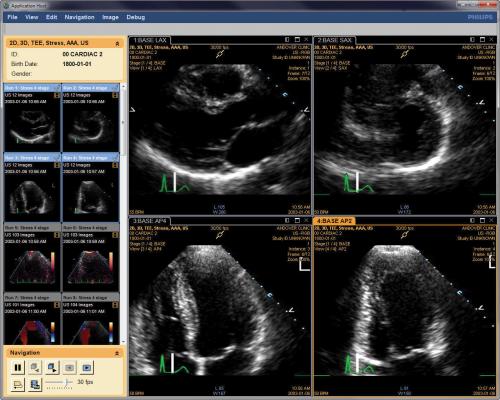

In the new study, designed to shed light on the subject, the Johns Hopkins researchers used imaging technology to study the pumping and relaxing activity of hearts in the sickest 10 percent of pregnant women with preeclampsia. A report on the study was published in the Journal of the American College of Cardiology on July 2.

All participants underwent echocardiography to make images of the heart's chambers at about 33 weeks of pregnancy. Results of the imaging showed that women with severe preeclampsia had higher contraction pressures in the right ventricles of their heart, and an average 31 millimeters of mercury compared to the healthy group with 22 millimeters of mercury. The ventricles are the two lower pumping chambers of the heart's four sections.

Because the right ventricle "shortens" or contracts during heart contraction, researchers were able to see a 5 percent difference in the change of the heart's shape in those with severe preeclampsia compared with healthy controls.